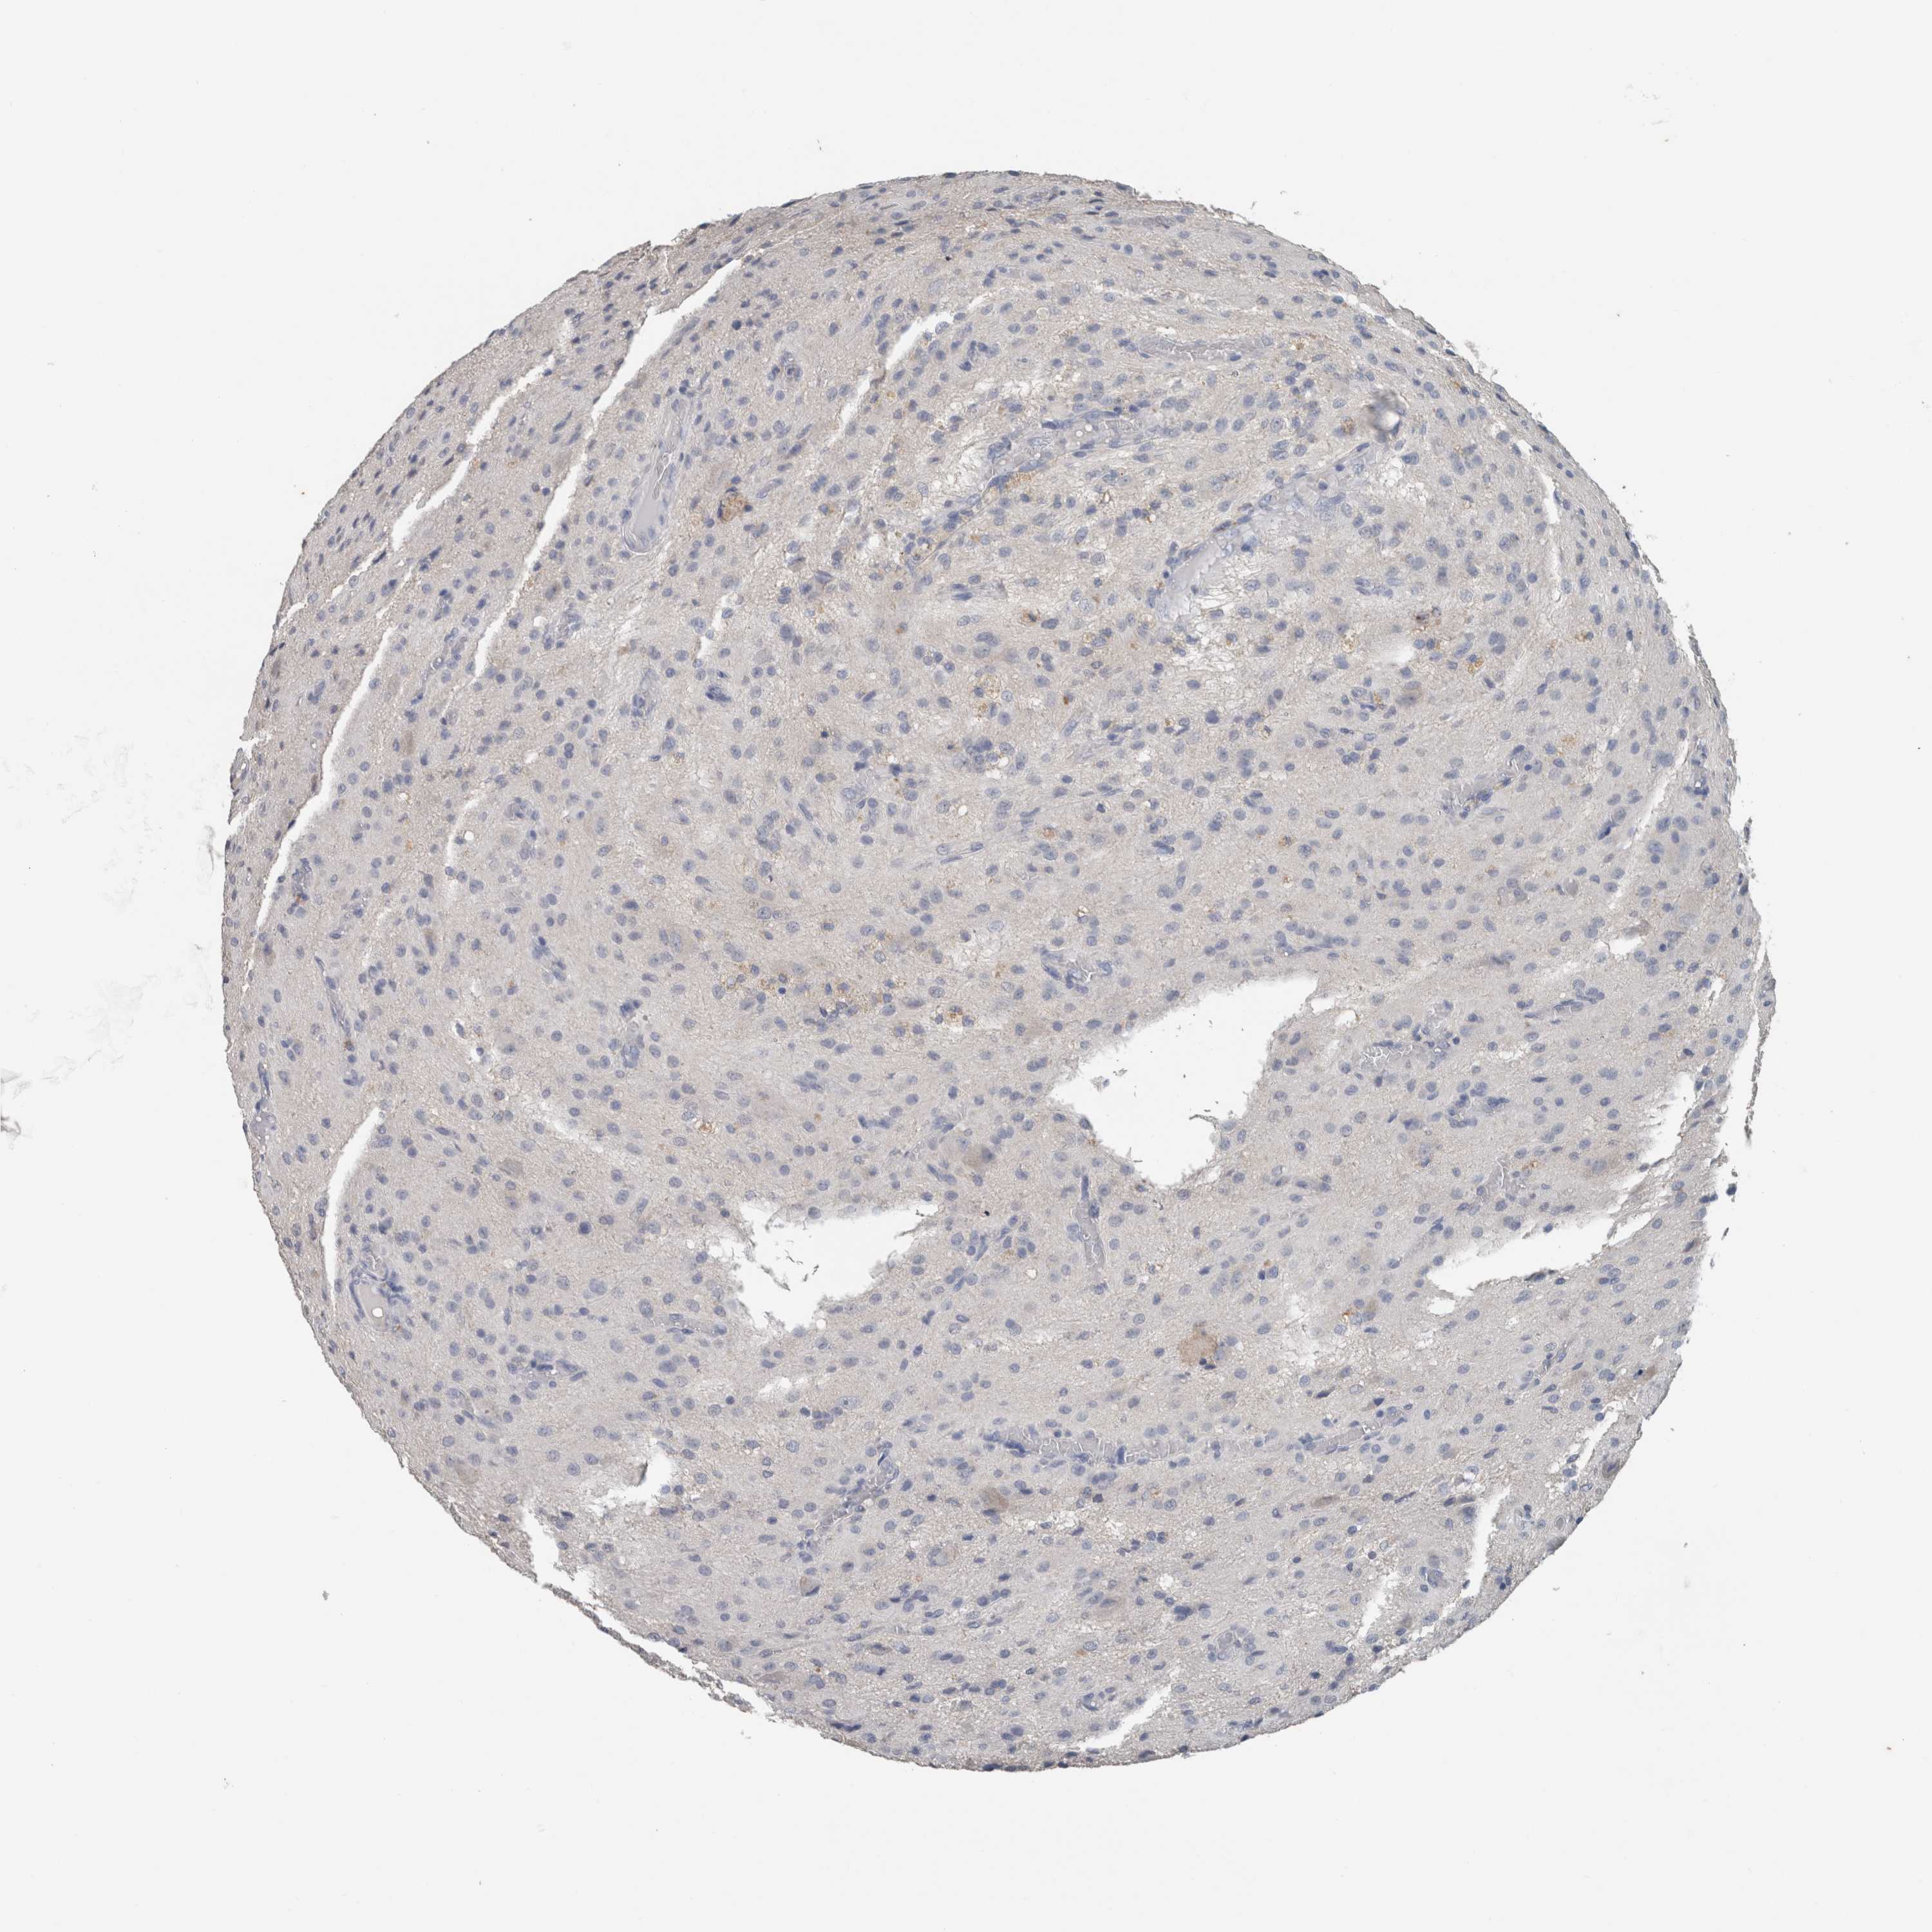

GLIOMA - Protein expressioni

A mouse-over function shows sample information and annotation data. Click on an image to view it in a full screen mode. Samples can be filtered based on level of antibody staining by selecting one or several of the following categories: high, medium, low and not detected. The assay and annotation is described here.

Antibody stainingi

Antibody staining in the annotated cell types in the current human tissue is reported as not detected, low, medium, or high, based on conventional immunohistochemistry profiling in selected tissues. This score is based on the combination of the staining intensity and fraction of stained cells.

Each image is clickable and will lead to virtual microscopy that enables deeper exploration of all samples and also displays staining intensity scores, fraction scores and subcellular localization as well as patient and tissue information for each sample.

Antibody HPA024343

Antibody CAB026182

Staining

High

Medium

Low

Not detected

Intensity

Strong

Moderate

Weak

Negative

Quantity

>75%

75%-25%

<25%

None

Location

Nuclear

Cytoplasmic/membranous

Cytoplasmic/membranous,nuclear

Glioma, malignant, High grade

Glioma, malignant, Low grade